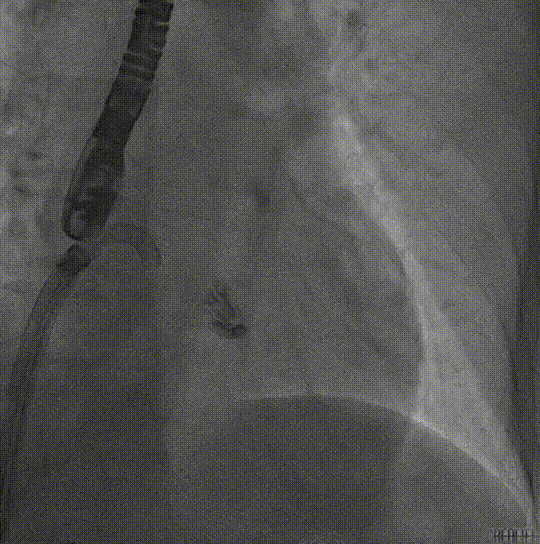

DSA